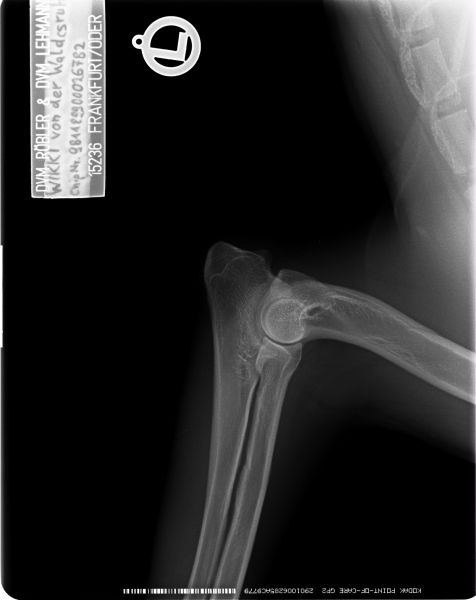

Auswertung der Röntgenbilder von Wikki  aus Augsburg:

HD- fast normal; ED-normal